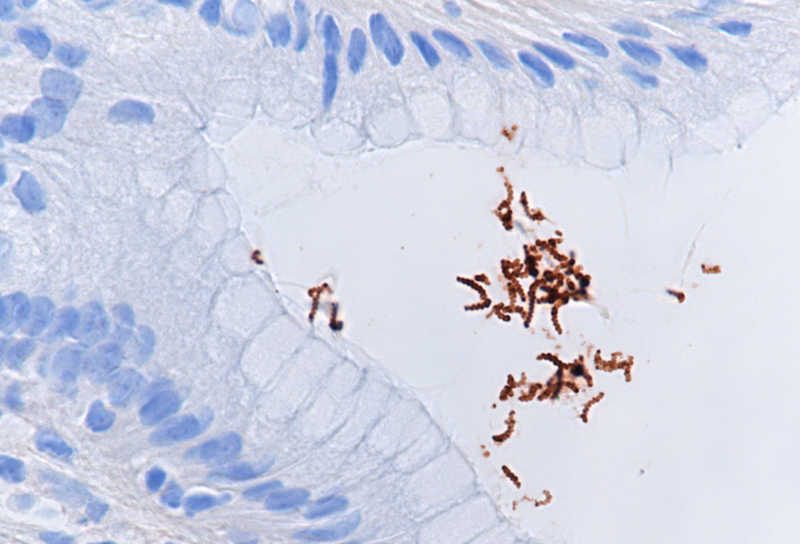

Histologic examination showed moderate chronic antrum gastritis with mild focal neutrophilic inflammation and small superficial mucosal erosions (Panel A). In the mucus layer close to the surface epithelium and in several of the foveolar pits, large, thin, corkscrew-shaped bacilli were found (Panel B) that could be highlighted with a H. pylori immunostain (Panels C-D). The characteristic morphology of the bacterial structures and their cross-reactivity with the anti-H. pylori antibody were consistent with Helicobacter heilmannii.